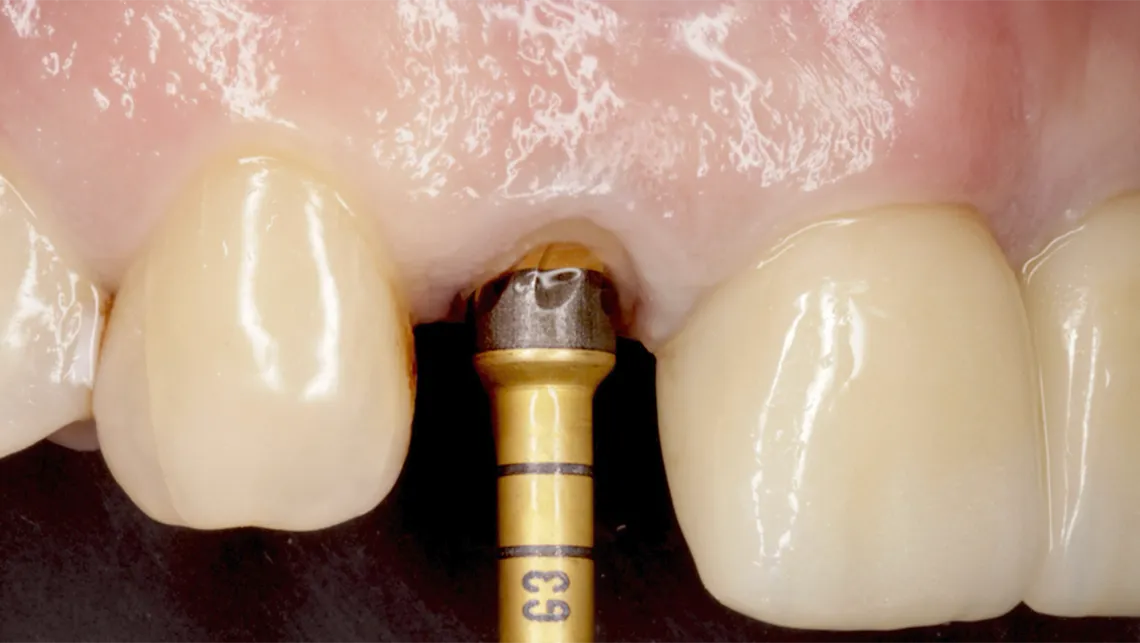

Asimismo, la técnica SPOT (Selective Preservation of Tooth) representa una evolución del concepto de Socket Shield, al estandarizar la preparación del escudo radicular y la osteotomía mediante oseodensificación. Este enfoque permite preservar tejidos duros y blandos, mejorar la estabilidad primaria y optimizar la cicatrización temprana (figura 18).

Fig. 13.  Fotografía del control de estabilidad biológica con sistema Osstell, tras la instalación de un implante postextracción Galimplant con oseodensificación

Fig. 15. SPOT, implante instalado

Fig. 16. Implante cicatrizado a 9 semanas